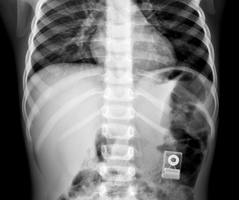

Diagnostic System with Piezo Electric Transformer for Ultrasound

Secondary Coils for Magnetic Resonance Imaging

Wireless Charger for Medical Devices